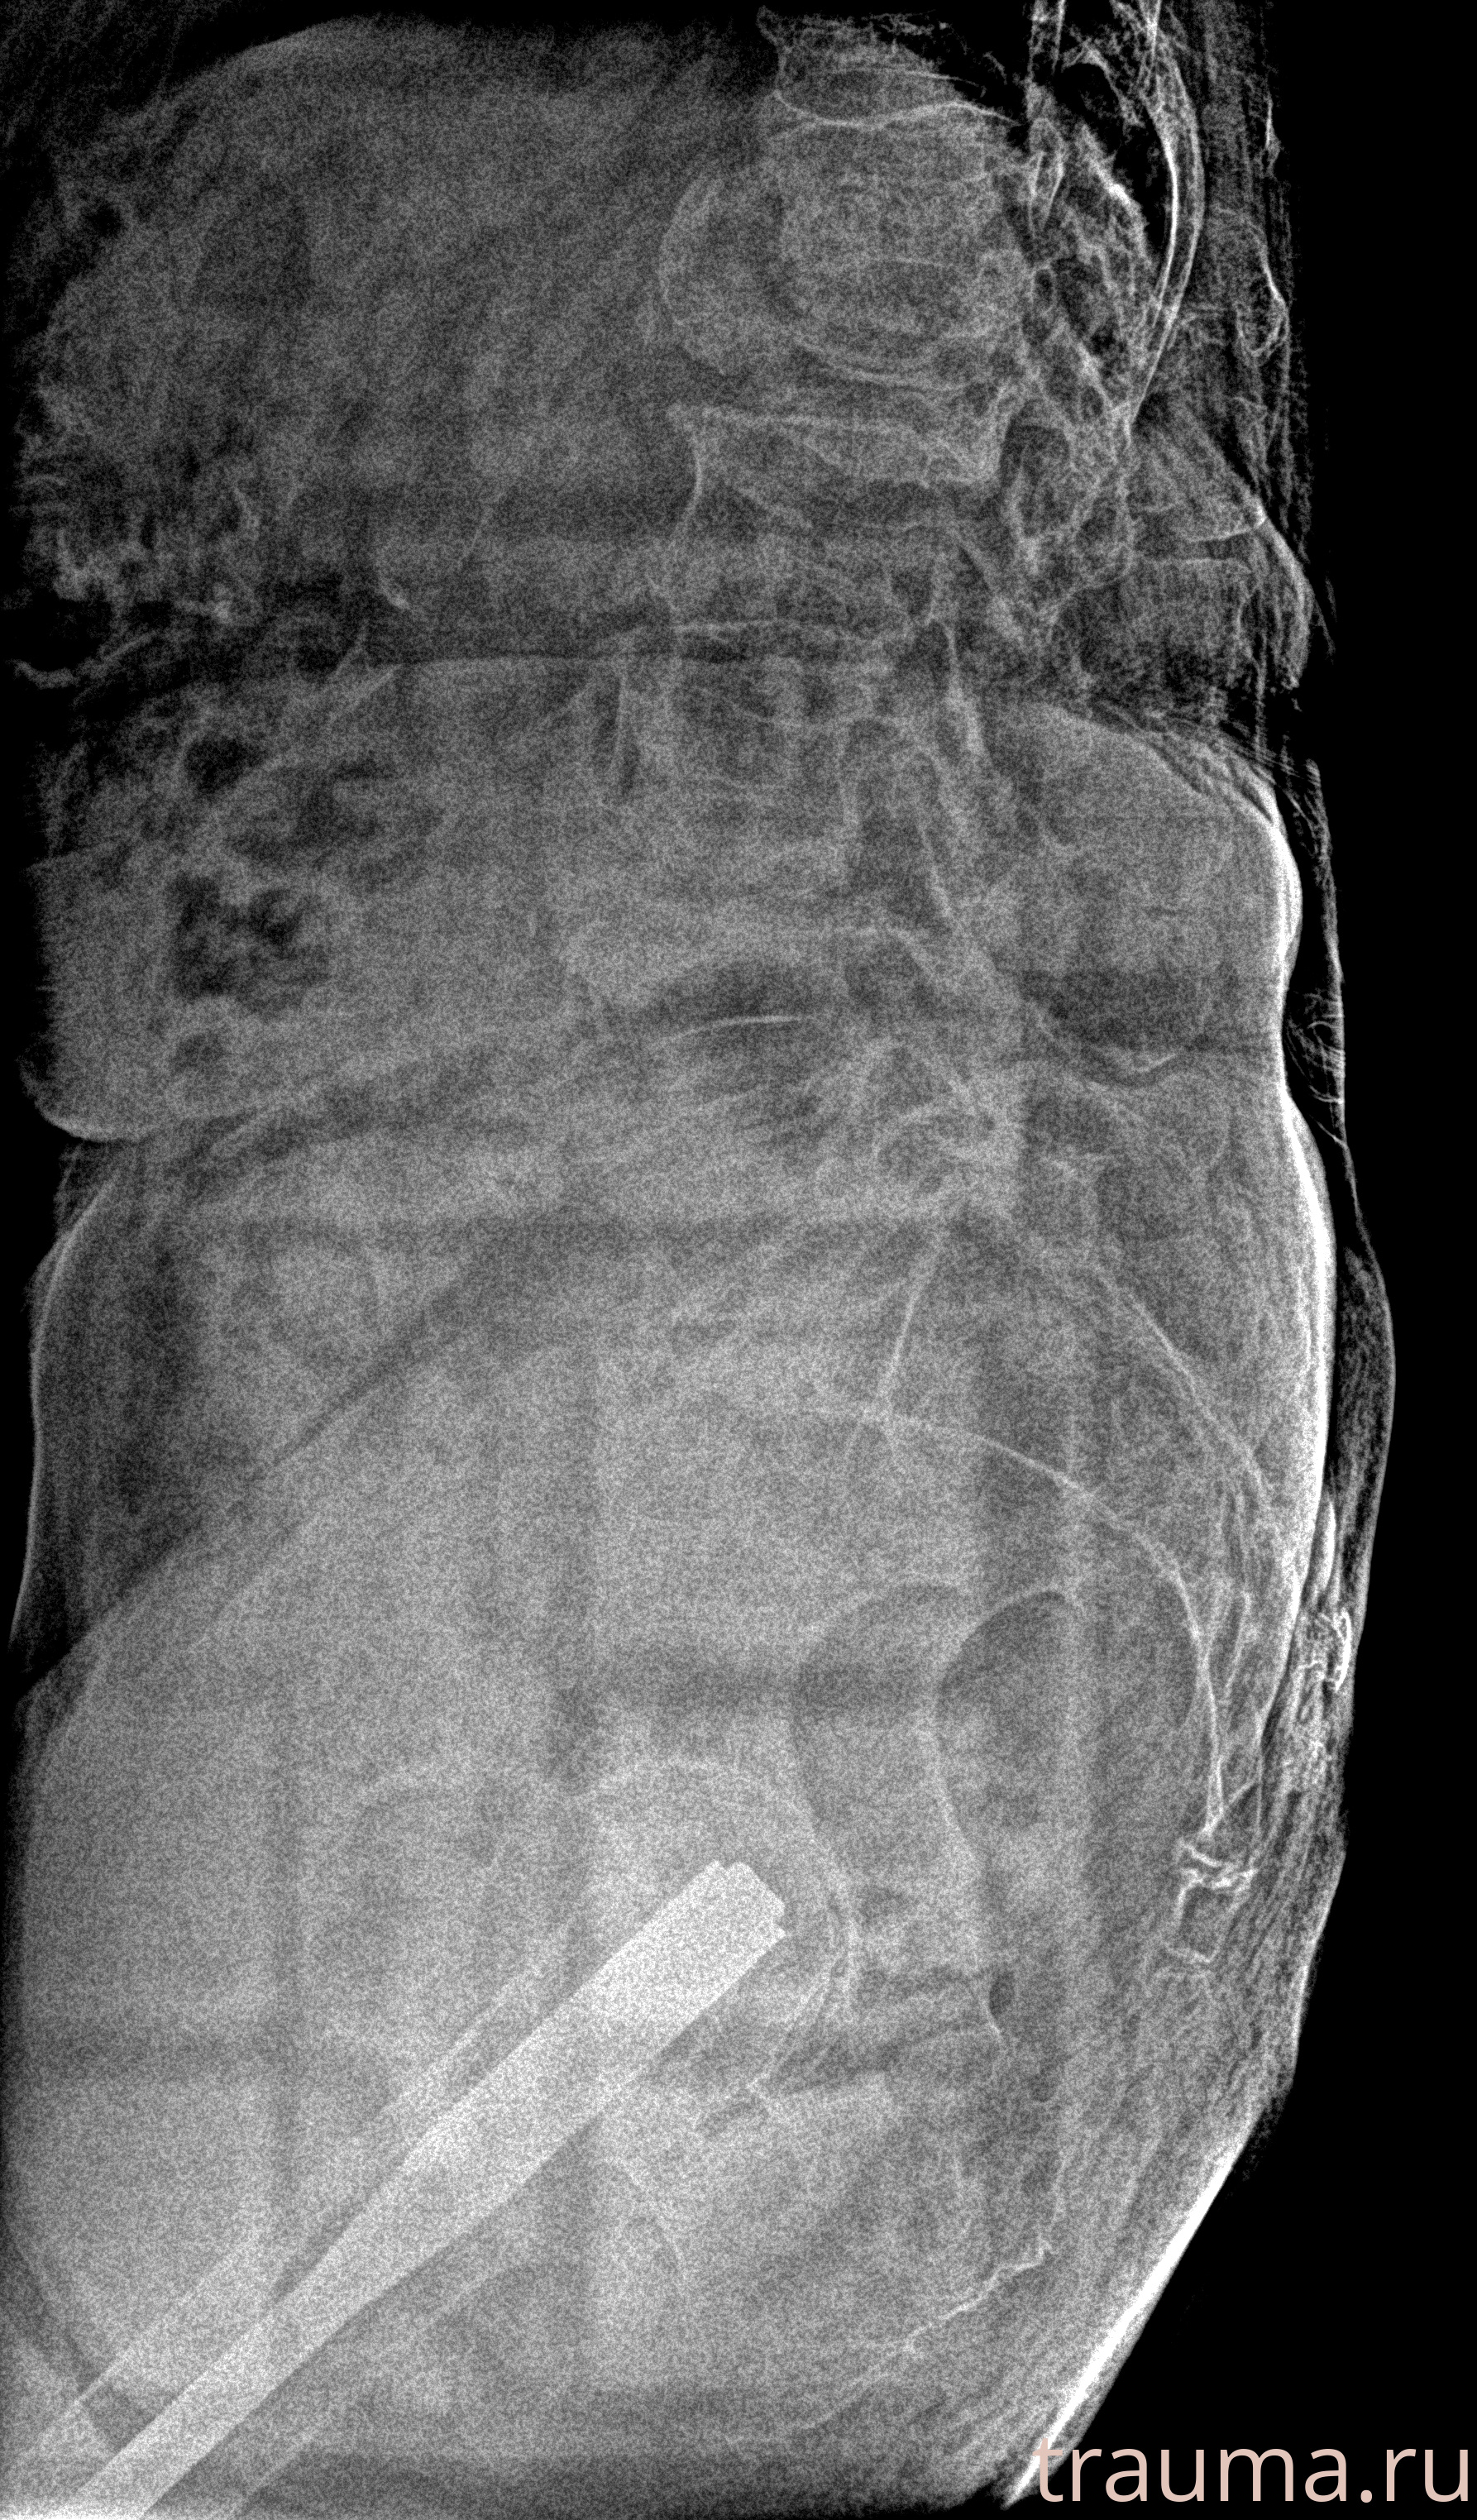

Рентген на дому: по вашему адресу приезжает врач-рентгенолог, травматолог-ортопед с мобильным рентгеновским аппаратом, проводит диагностику травмы или заболевания, делает необходимые рентгенограммы, дает рекомендации по дальнейшему лечению. Получить качественные снимки в домашних условиях возможно благодаря уникальной методике, разработанной МосРентген Центром для института  Склифосовского